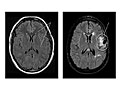

Magnetic resonance imaging (MRI) is a test that uses a magnetic field and pulses of radio wave energy to take pictures of the head. In many cases, MRI gives information that can't be seen on an X-ray, ultrasound, or computed tomography (CT) scan.

For an MRI of the head, you lie with your head inside a special machine (scanner) that has a strong magnet. The MRI can show tissue damage or disease, such as infection or inflammation, or a tumour, stroke, or seizure. Information from an MRI can be saved and stored on a computer for more study. Photographs or films of certain views can also be made.

Magnetic resonance imaging (MRI) of the head

Normal:

All structures of the head—the brain, its vessels, spaces, nerves, and surrounding structures—are normal.

No abnormal growths, such as tumours, in or around the brain are present.

No bleeding, abnormal blood vessels (AV malformations), abnormal pockets of fluid, blockage in the flow of blood, or bulges in the blood vessels (aneurysm) are present.

No signs of infection or inflammatory disease, such as encephalitis or meningitis, are present.